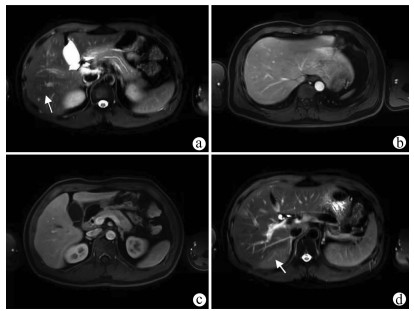

以亚急性肝衰竭为首发表现的IgG4相关性自身免疫性肝炎1例报告

2022, 38(1): 170-173. DOI: 10.3969/j.issn.1001-5256.2022.01.028

摘要(1571) HTML (431) PDF (3941KB)(81)

摘要: